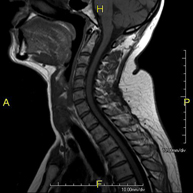

Prova diagnòstica no invasiva que consisteix en l'obtenció d'imatges d'alta definició anatòmica de la columna cervical mitjançant l'ús d'un camp electromagnètic i ones de ràdio (com un emissor i un receptor). No utilitza radiació ionitzant. Indicacions: traumatisme, degeneració de la columna, hèrnies. - RM de columna dorsal

Prova diagnòstica no invasiva que consisteix en l'obtenció d'imatges d'alta definició anatòmica de la columna cervical, mitjançant l'ús d'un camp electromagnètic i ones de ràdio (amb un emissor i un receptor). No utilitza radiació ionitzant. Indicacions: traumatisme, degeneració de la columna i hèrnies. - RM Columna Dorsal

Prova diagnòstica no invasiva que consisteix en l'obtenció d'imatges d'alta definició anatòmica de la columna dorsal, mitjançant l'ús d'un camp electromagnètic i ones de ràdio (amb un emissor i un receptor). No utilitza radiació ionitzant. Indicacions: traumatisme, problemes degeneratius, hèrnies i tumors. - RM Columna Lumbar

Prova diagnòstica no invasiva que consisteix en l'obtenció d'imatges d'alta definició anatòmica de la columna lumbar i sacre mitjançant l'ús d'un camp electromagnètic i ones de ràdio (amb un emissor i un receptor). No utilitza radiació ionitzant. Indicacions: traumatismes, ciàtica, hèrnies discals, tumors i infeccions. - RM de Sacre-còccix